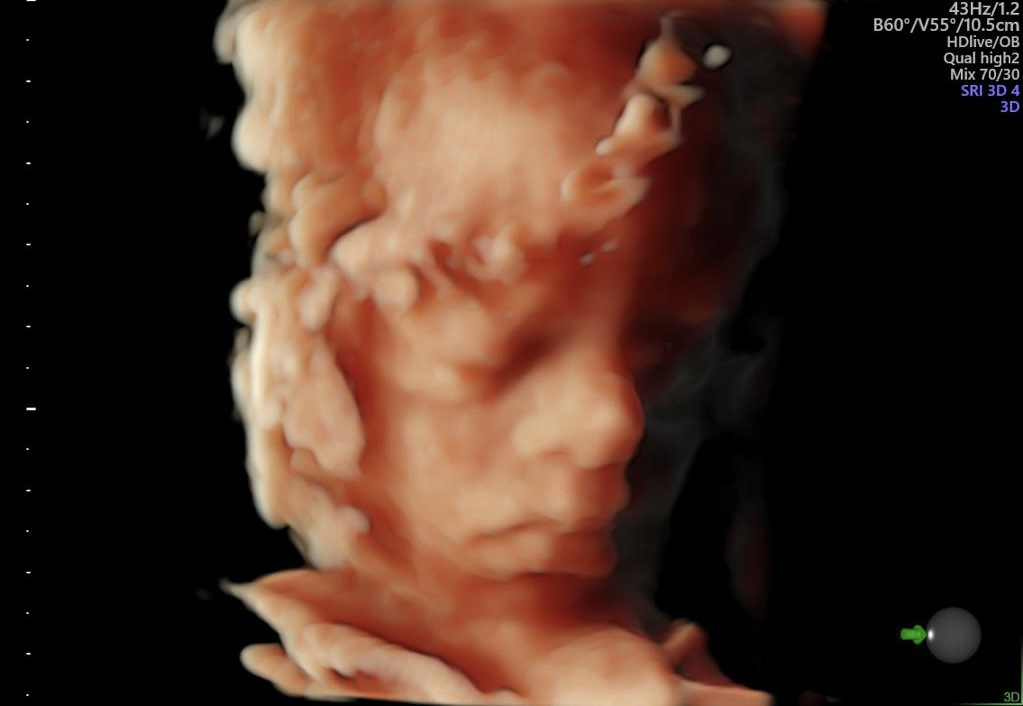

6EB4790C-CBAA-4008-B322-E554AD00A703